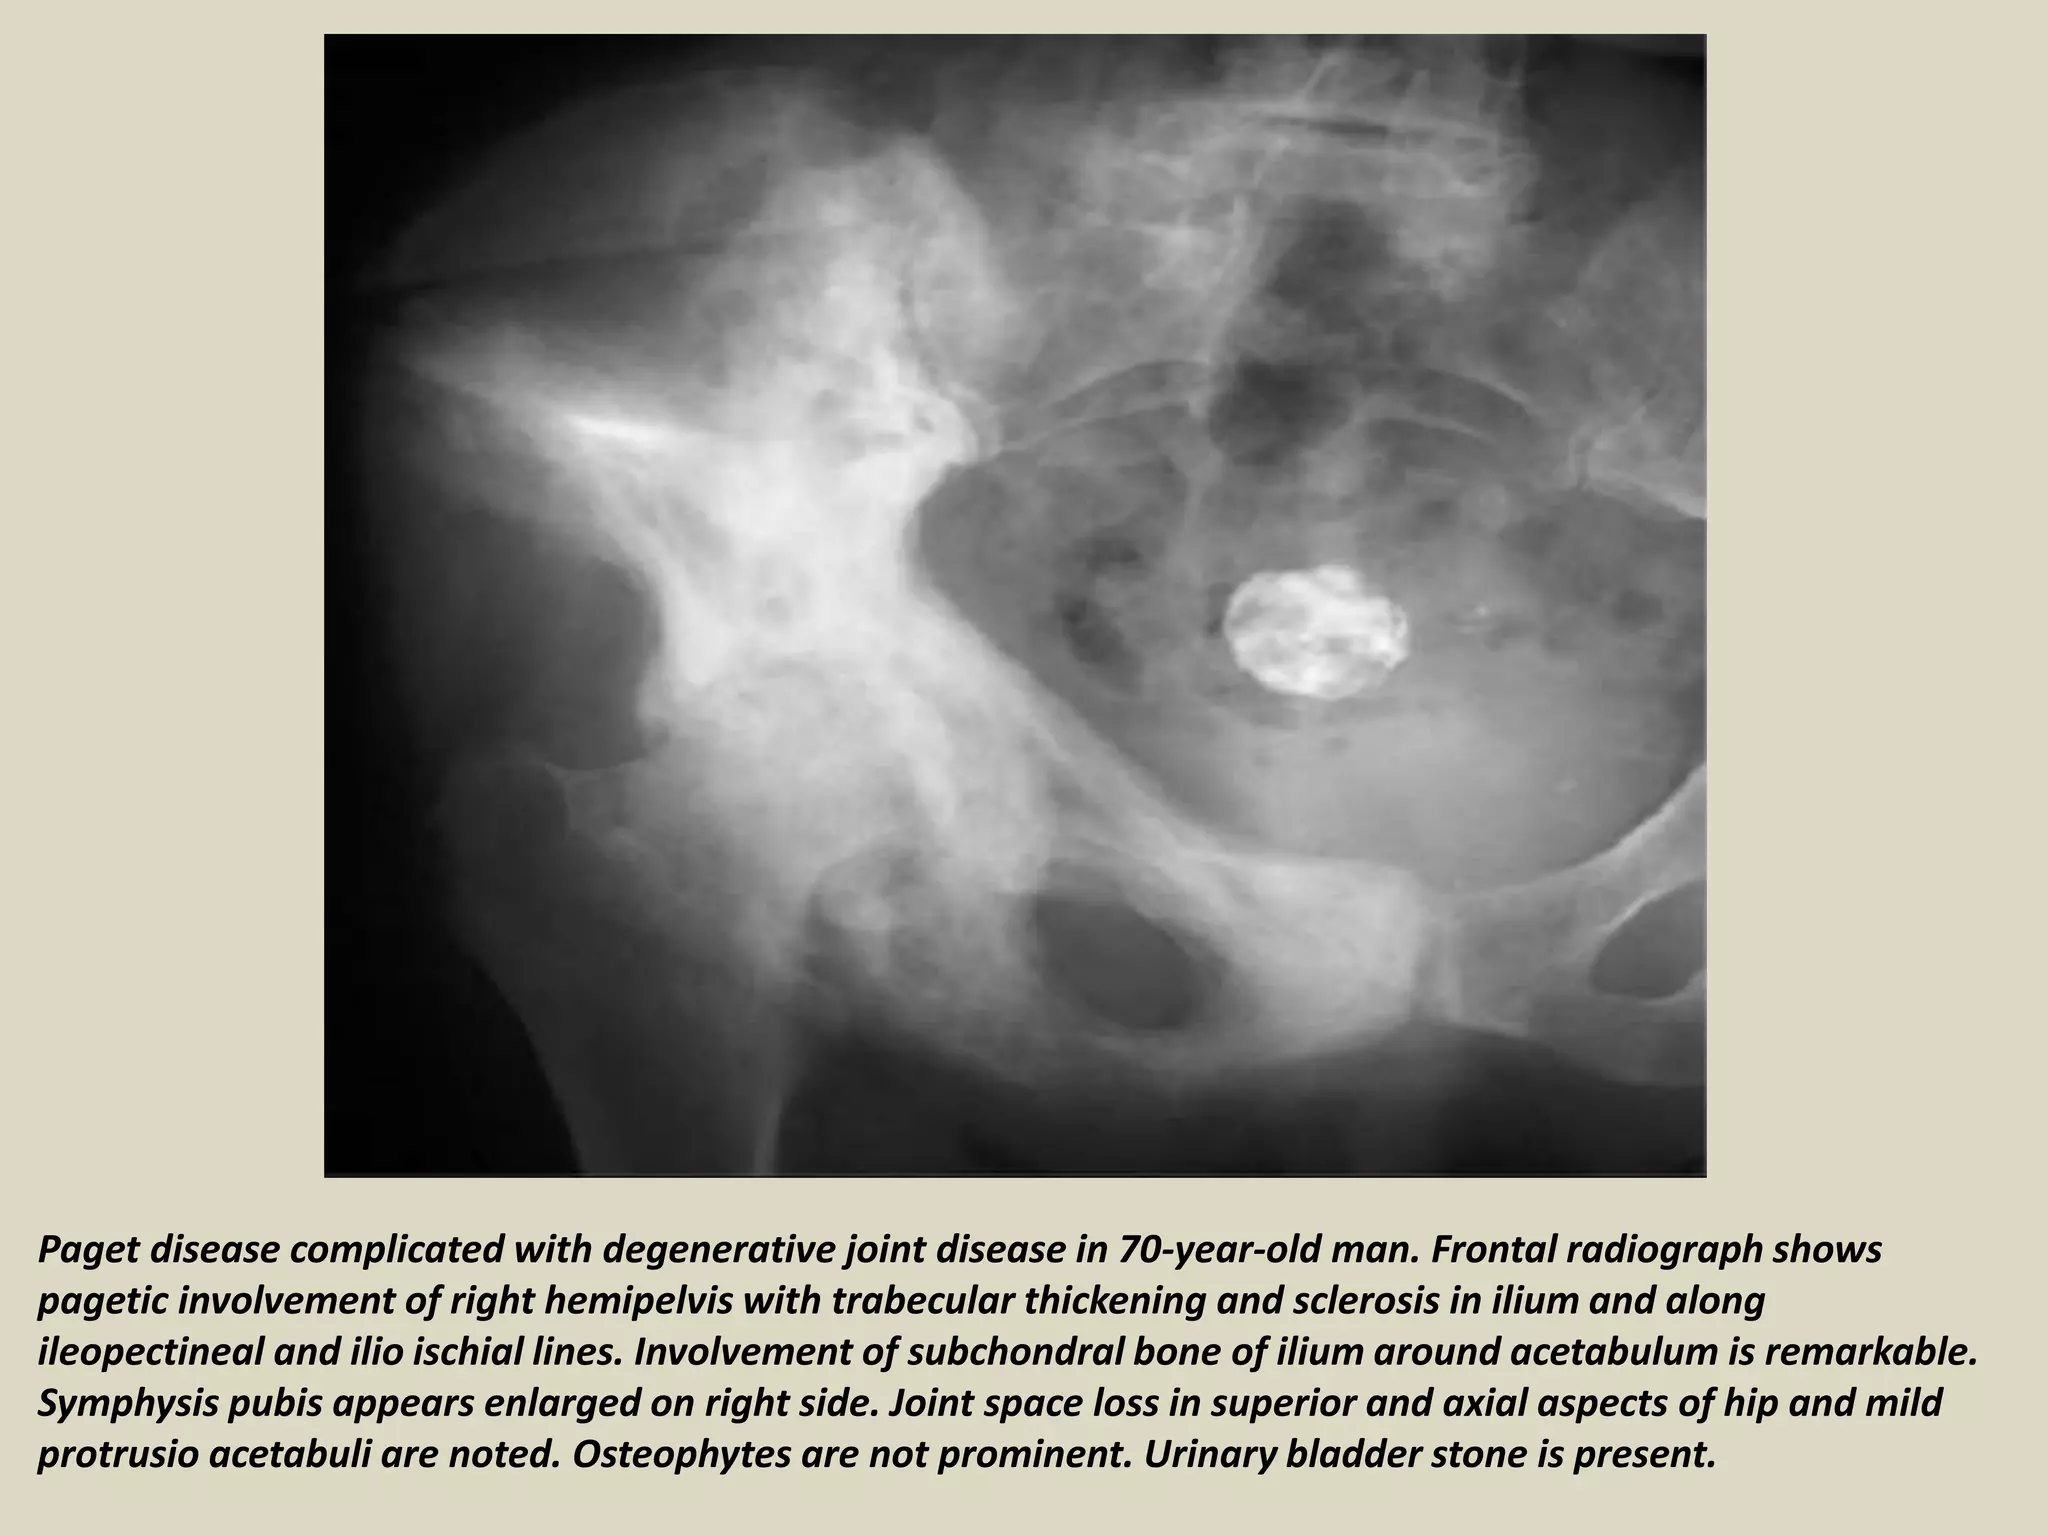

Paget disease complicated with degenerative joint disease in 70-year-old man. Frontal radiograph shows

pagetic involvement of right hemipelvis with trabecular thickening and sclerosis in ilium and along

ileopectineal and ilio ischial lines. Involvement of subchondral bone of ilium around acetabulum is remarkable.

Symphysis pubis appears enlarged on right side. Joint space loss in superior and axial aspects of hip and mild

protrusio acetabuli are noted. Osteophytes are not prominent. Urinary bladder stone is present.